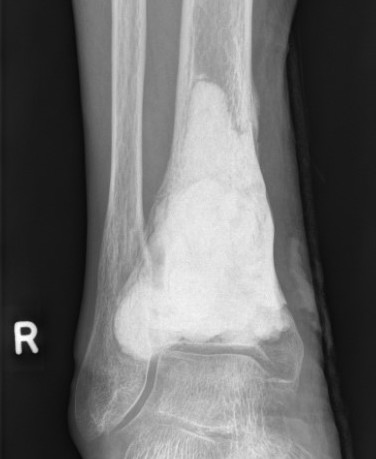

Distal Radius

Abuhejleh et al Eur J Orthop Traumatol Surg 2020

- 57 patients with GCT's of distal radius

- 29% (10/34) recurrence with intra-lesional treatement but no complications

- 4% (1/23) recurrence with wide resection / arthrodesis but 30% complication rate

- increased risk recurrence for Grade 3

- wide resection / arthrodesis should be reserved for grade 3

Koucheki et al Eur J Orthop Traumatol Surg 2023

- systematic review of 13 studies and 373 patients

- increased local recurrence with intralesional versus en-bloc resection

- especially Grade 3

- increased complications and poorer function with en-bloc resection

Distal radius GCT treated with en bloc resection and allograft reconstruction, followed by late wrist subluxation